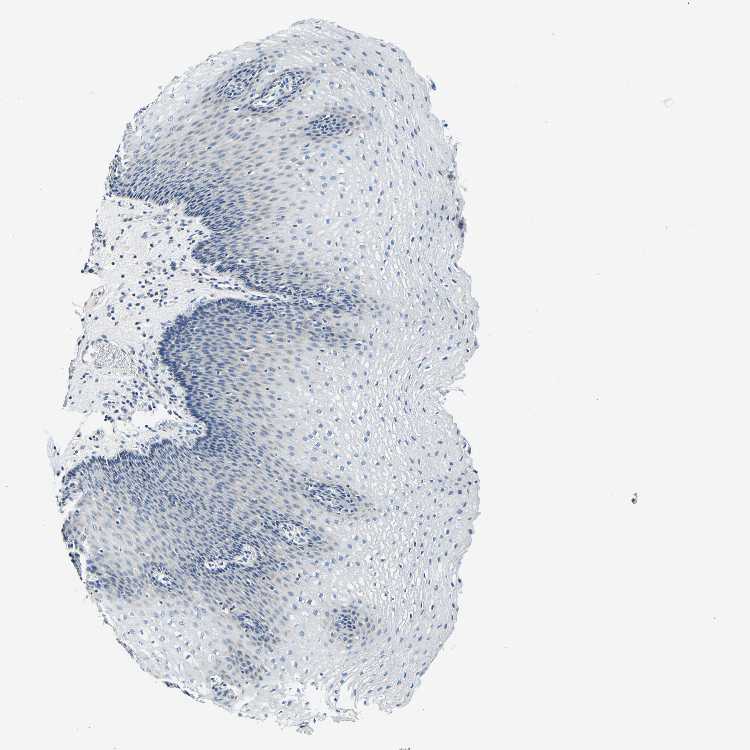

ESOPHAGUS - Antibody stainingi

Antibody staining in the annotated cell types in the current human tissue is reported as not detected, low, medium, or high, based on conventional immunohistochemistry profiling in selected tissues. This score is based on the combination of the staining intensity and fraction of stained cells.

Each image is clickable and will lead to virtual microscopy that enables deeper exploration of all samples and also displays staining intensity scores, fraction scores and subcellular localization as well as patient and tissue information for each sample.

Antibody HPA012373

Squamous epithelial cells Not detected